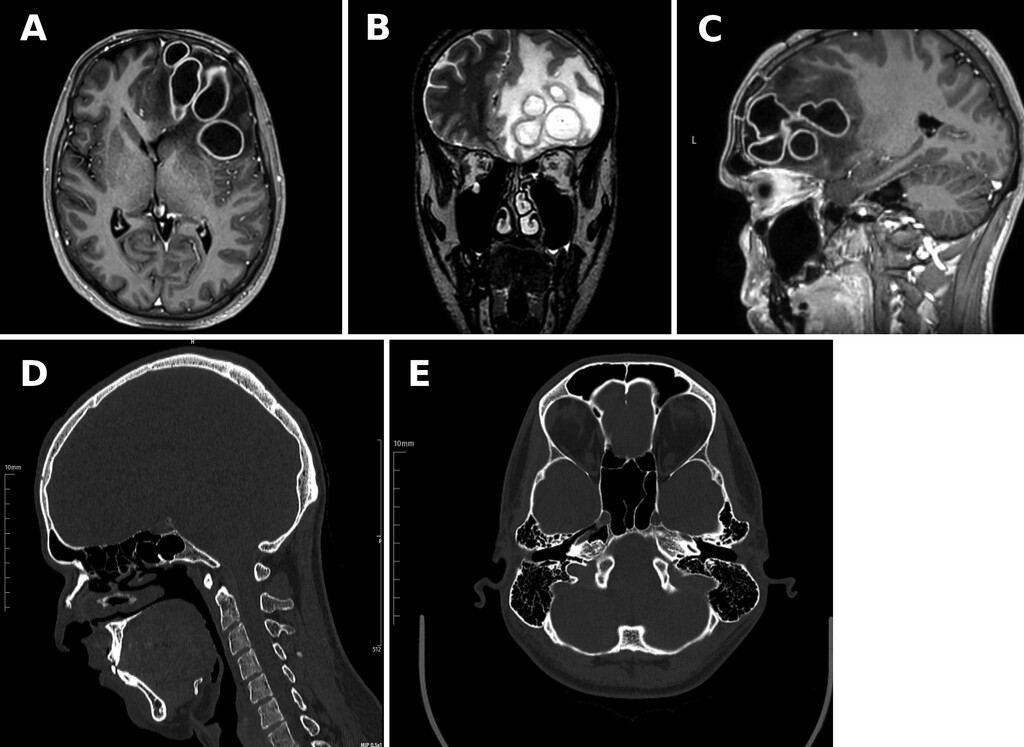

2.病原学检测与抗感染治疗:抽吸物培养检出麻疹孪生球菌和玫瑰考克菌,二者均为少见的共生菌,可引发侵袭性感染。患者接受万古霉素、头孢曲松、甲硝唑静脉抗感染治疗1个月。耳鼻喉科鼻内镜检查未见鼻窦感染残留。术后第1个月末,患者仍在住院并接受静脉抗生素治疗,神经系统查体正常,炎症指标较前有所改善(CRP 20 mg/L,ESR 34 mm/hr)。然而,随着头痛进行性加重,复查头颅CT及MRI显示,左侧额叶出现复发性包膜完整的环形强化脓肿,伴周围水肿(图2)。

图2:A:增强T1加权MRI,示左侧额叶复发性环形强化病灶。B:T2加权MRI,示病灶周围血管源性水肿较前加重。C:增强T1加权MRI,示复发病灶上下范围(颅尾方向)。D:CT示额窦后壁局部骨质缺损。E:CT证实局部骨质缺损并向颅内延伸。